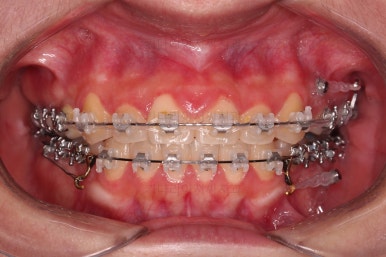

부산치아교정 이번 치료의 핵심인데요.

결손 부위에 미니스크류를 이용해서 뒤쪽 어금니들을 결손 부위로 앞으로 앞으로 계속 당겨줍니다.

얼굴모습에서의 중앙선도 지속저으로 체크하면서 한 쪽으로 치우침 없이 마무리를 해야 하고요.

틈새가 줄어들 때 까지 같은 작업을 반복합니다.

점점 틈새가 붙어가는게 보이죠?

계속 반복합니다.

틈새는 거의 다 붙어가는데 교합이나 중앙선 등을 위해 추가적으로 밀고 당기기를 해줍니다.